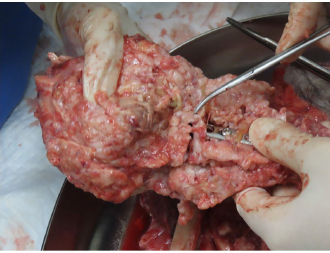

AbstractBackground: There are few detailed reports on implant-associated sarcoma in dogs; however, loose implants, metal type, and infection have not been shown as specific risk factors for this condition. Case Description: A 14-year-old spayed female Labrador retriever was referred to our hospital with a main complaint of chronic right hind lameness after previous tibial fracture repair. On radiographs, rupture of the bone plate and screws with swelling of the surrounding soft tissue was observed, and osteosarcoma (OSA) was diagnosed after histopathological examinations. During amputation surgery, a plastic band was found associated with the implant. Conclusion: Veterinary surgeons should be aware of implant-associated OSA and refrain from using non-medical materials in the implants. Furthermore, they should recommend the removal of orthopedic implants after fracture repair. Keywords: Dogs, Fracture, Implant, Osteosarcoma, Repair. IntroductionOsteosarcoma (OSA) is a highly aggressive mesenchymal tumor that comprises at least 85% of canine bone tumors (Egenvall et al., 2007) and tends to occur in larger individuals, and the most common site in dogs is in the appendicular skeleton near metaphyses (Morello et al., 2011). Several studies have suggested that OSAs result from abnormalities in osteoblast differentiation, as mesenchymal stem cells differentiate through osteoprogenitor and osteoblast phases before becoming mature osteocytes (Tang et al., 2008). Osteoblastic features are common in OSA, suggesting that early disruption of osteogenic differentiation may occur during sarcoma development (Tang et al., 2008). Furthermore, this process is sometimes initiated by the presence of orthopedic implants (Murphy et al., 1997; Rose et al., 2005). Loose implants, metal type, and infection have not been shown to be specific risk factors of implant-associated sarcoma (Sinibaldi et al., 1976; Kenecht et al., 1978; MacDonald et al., 2012). There have been a few reports on implant-associated sarcoma in dogs, albeit with minimal information (Burton et al., 2015; Arthur et al., 2016). Our case describes canine implant-associated OSA at the site of a previous fracture, repaired with bone plate and screws and an unknown plastic band. Case DetailsA 14-year-old spayed female Labrador retriever weighing 21.3 kg was referred to our hospital with a main complaint of chronic right-hind lameness. This patient had undergone surgery for right tibial fracture repair with implantation of bone plate and screws at a referral hospital 12 years ago. The patient showed no appetite, was not drinking, and was lethargic, with a body condition score of 1/5. The patient was unable to stand up on her own, her right hind limb was mostly weak, and she was unable to move independently using her left side. The patient’s state of consciousness was normal. On physical examination, her vital signs were normal (temperature: 38.1°C, pulse 104 beats/minutes with no heart murmur, respiratory rate with normal lung sounds: 32 beats/minutes). The mucous membrane showed a pale color because of severe anemia (packed cell volume 20.4%). In addition, the capillary refill time was delayed by <3 seconds, suggesting severe dehydration. The patient showed swelling and was warm to the touch from the right tibia to the femur, with a swollen right popliteal lymph node, which presented with a ruptured mass lesion approximately 7 × 10 cm in size. The thoracic radiograph was normal (Fig. 1). However, the right hind limb radiograph showed an osteolytic lesion accompanying the ruptured implant and loosening of the plate and screws, with surrounding soft tissue swelling (Fig. 2). Fine needle aspiration from this site suggested OSA (data not shown). Although we could not perform angiographic computed tomography because of the owner’s dissent, we performed amputation from the hip joint on the same day. Gross morphology showed severe inflammation surrounding soft tissues, the rupture of the stainless-steel bone plate, and we noted a non-medical band at the right tibia (Fig. 3). The patient was formally diagnosed with OSA after histopathological examinations (Fig. 4). After 24 hours hospitalization, we administered ampicillin potassium (20 mg/kg, BID) intravenously and prednisolone (0.5 mg/kg, SID) subcutaneously for postoperative care. Also, 24 hours continuous rate infusion of fentanyl (5 μg/kg/minutes) in lactated Ringer’s solution was used for analgesia. The patient was discharged to the owner the day after surgery for home care. The owner refused postoperative radiation therapy and chemotherapy. Unfortunately, this patient died 1 month after amputation.

No metastasis was observed. Fig. 2. Limb radiographs. The right tibia showed an osteolytic lesion with rupture of orthopedic plate, loosening of screws, and also soft tissue swelling. DiscussionOrthopedic implants are commonly used in small animal patients, including dogs, and hence an awareness of potentially serious complications is important. In a study of more than 19,000 open fracture restoration cases in canines occurring between 1970 and 2000, only 15 cases of OSA had occurred at the site of fracture restoration. In other words, the incidence of OSA at a fracture site was less than 0.08% (Arthur et al., 2016). Although long-term inflammation is recognized as a contributing factor to creating an environment promoting tumorigenesis, this relationship has not been demonstrated in reports of implant-associated malignancy. While the effects of implant composition and wear have received great attention, the role of chronic inflammation in the development of sarcoma remains a point of interest (Visuri et al., 2006). Many initiating factors have been hypothesized to play a role in the development of implant-associated sarcoma. Researchers have shown that many implant materials, including commonly used stainless steel and titanium, have potentially carcinogenic properties (Kirkpatrick et al., 2000). Consequently, some surgeons suggest the removal of orthopedic implants after fracture repair. In our case, non-medical bands had been used to surround the bone plate, probably leading to severe inflammation and resulting in the occurrence of OSA at the fracture site. In veterinary medicine, there are few reports about canine implant-associated neoplasia (Burton et al., 2015; Arthur et al., 2016). In a retrospective study of 16 cases of canine implant-associated tumors, it was determined that tumors developed an average of 5.5 years after implant placement. In addition, the hind limbs [tibia (8/16) and femur (5/16)] were favored; 15 of the 16 cases developed in the bone trunk and 13 were OSAs (Burton et al., 2015). Our case showed the same features as those documented in the previous report (Burton et al., 2015).

Fig. 3. An unusual plastic band was found around the orthopedic plate.

Fig. 4. Histopathological diagnosis was OSA. Although the interaction between vinyl chloride and OSA has not been reported in dogs, various chemicals (fluoride, beryllium, and vinyl chloride), exposure to radiation, and viruses have been identified as factors, inducing OSA, in humans (Operskalski et al., 1987). The patient in this case report did not have radiation therapy, no medical record of virus infection, or family history of OSA. Hence, we concluded that the vinyl chloride bands might be associated with the development of OSA. In summary, veterinary surgeons should be able to recognize implant-associated OSA and should be discouraged from using non-medical materials in implants. Furthermore, we recommend the removal of orthopedic implants after fracture repair. Conflict of interestThe authors declare that there is no conflict of interest. Authors’ contributionsMitsuhiro Isaka, Daiki Kokubo, and Toshikazu Sakai conceived and performed the procedure, drafted and revised the manuscript, and approved the final version. ReferencesArthur, E.G., Arthur, G.L., Keeler, M.R. and Bryan, J.N. 2016. Risk of osteosarcoma in dogs after open fracture fixation. Vet. Surg. 45, 30–35. Burton, A.G., Johnson, E.G., Vernau, W. and Murphy, B.G. 2015. Implant-associated neoplasia in dogs:16 cases (1983-2013). J. Am. Vet. Med. Assoc. 247, 778–785. Egenvall, A., Nodtvedt, A. and von Euler, H. 2007. Bone tumors in a population of 400000 insured Swedish dogs up to 10 y of age: incidence and survival. Can. J. Vet. Res. 71, 292–299. Kenecht, C.D. and Priester, W.A. 1978. Osteosarcoma in dogs: a study of previous trauma, fracture and fracture fixations. J. Am. Anim. Hosp. Assoc. 14, 82–84. Kirkpatrick, C.J., Alves, A. and Köhler, H., Kriegsmann, J., Bittinger, F., Otto, M., Williams, D.F. and Eloy. 2000. Biomaterial-induced sarcoma: a novel model to study preneoplastic change. Am. J. Pathol. 156, 1455–1467. MacDonald, D.J., Enneking, W.F. and Sundaram, M. 2002. Metal-associated angiosarcoma of bone: report of two cases and review of the literature. Clin. Orthop. Relat. Res. 396, 206–214. Morello, E., Martano, M. and Buracco, P. 2011. Biology, diagnosis and treatment of canine appendicular osteosarcoma: similarities and differences with human osteosarcoma. Vet. J. 89, 268–277. Murphy, S.T., Parker, R.B. and Woodard, J.C. 1997. Osteosarcoma following total hip arthroplasty in a dog. J. Small. Anim. Pract. 38, 263–267. Operskalski, E.A., Martin, S.P., Henderson, B. and Vicsher, B, R. 1987. A case control study of osteosarcoma. Am. J. Epidemiol. 126, 118–119. Rose, B.W., Novo, R.E. and Olson, E.J. 2005. Osteosarcoma at the site of a triple pelvic osteotomy in a dog. J. Am. Anim. Hosp. Assoc. 41, 327–331. Sinibaldi, K., Rosen, H. and Liu, S.K. and DeAngelis, M. 1976. Tumor associated with metallic implants in animals. Clin. Orthop. 118, 257–266. Tang, N., Song, W.X. and Luo, J., Haydon, R.C. and He, TC. 2008. Osteosarcoma development and stem cell differentiation. Clin. Orthop. Relap. Res. 466, 2114–2130. Visuri, T., Pulkkinen, P. and Paavolainen P. 2006. Malignant tumors at the site of total hip prosthesis. Analytic review of 46 cases. J. Arthroplasty. 21, 311–323. | ||